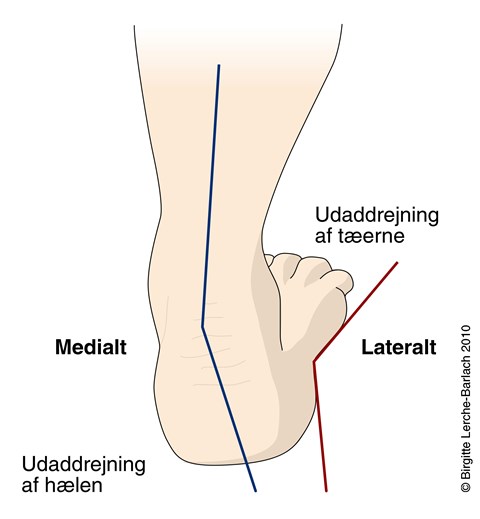

Diagnostik, evaluering og behandling platfødder børn | Ugeskriftet.dk

Diagnostik, evaluering og behandling platfødder børn | Ugeskriftet.dk

Diagnostik, evaluering og behandling platfødder børn | Ugeskriftet.dk

Diagnostik, evaluering og behandling platfødder børn | Ugeskriftet.dk